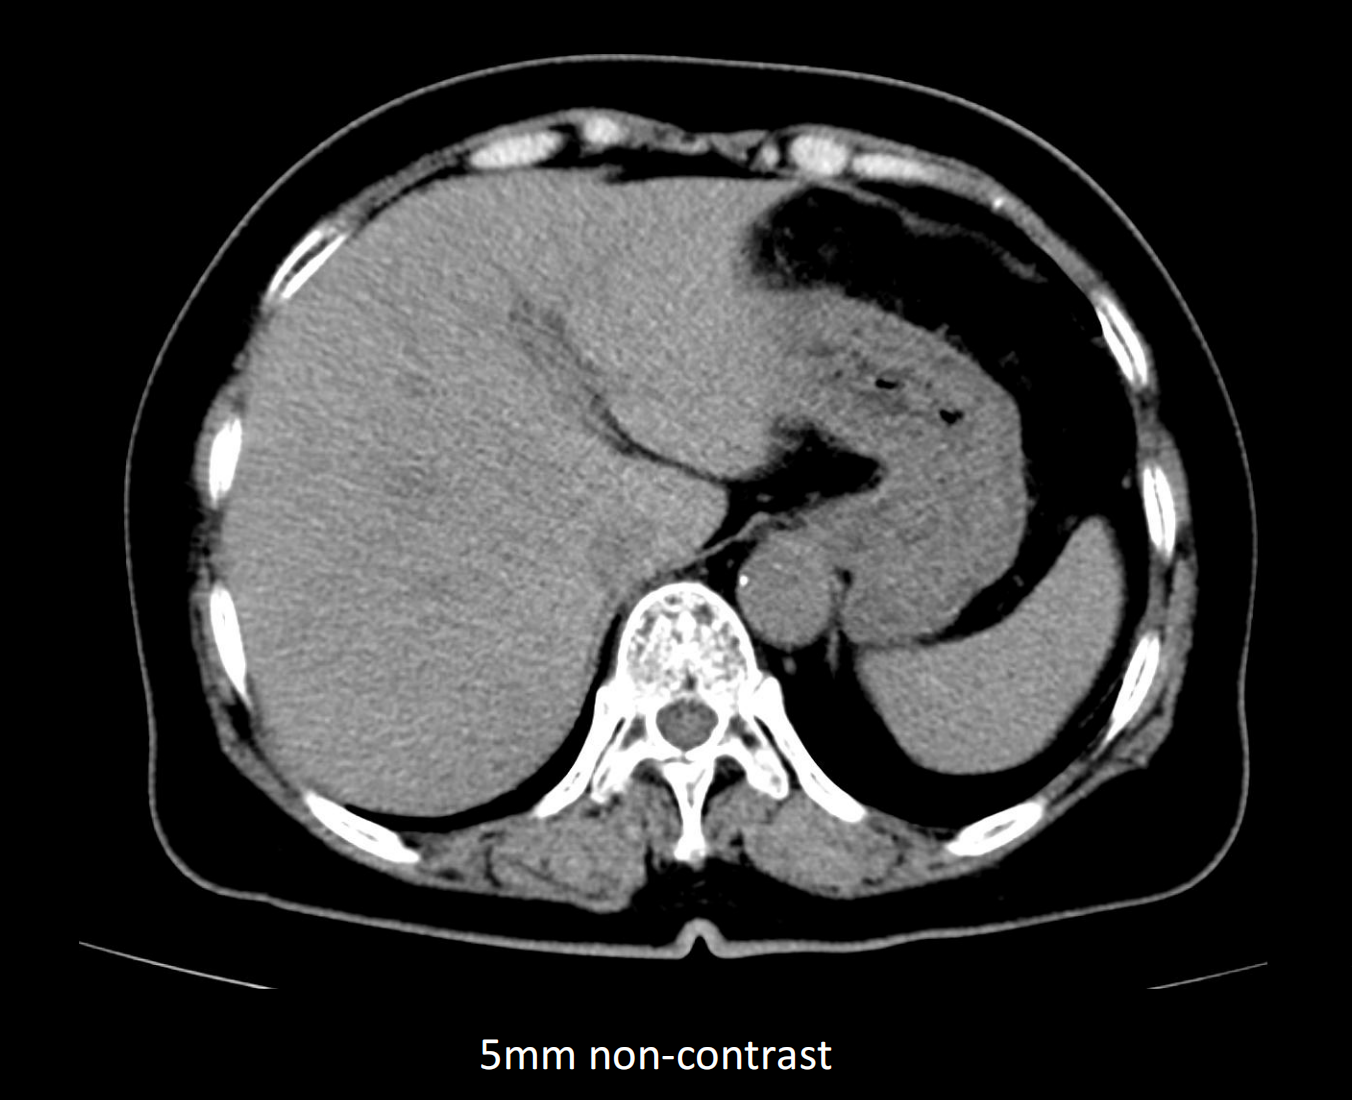

- Giải pháp chẩn đoán hình ảnh mô mềm tiên tiến cho khảo sát ổ bụng

- Tối ưu chất lượng hình ảnh chẩn đoán và giảm phơi nhiễm bức xạ

- Hỗ trợ đánh giá an toàn cho bệnh nhân

- Đảm bảo chất lượng hình ảnh chẩn đoán cao